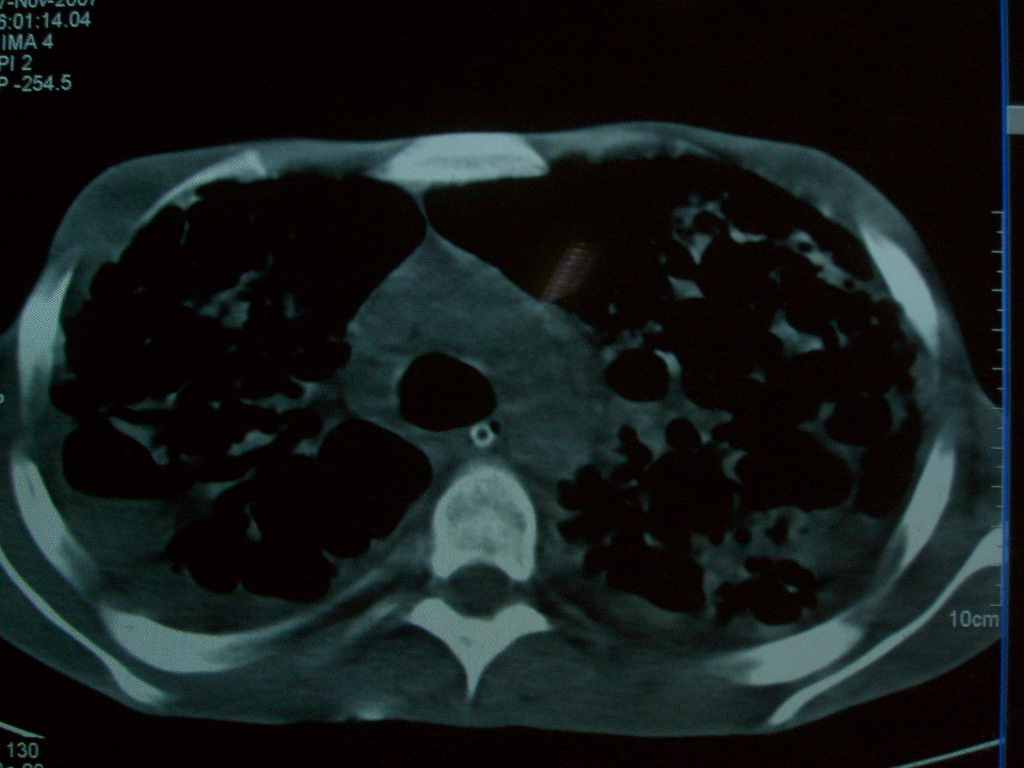

标题: CT10510:男.18岁,咳嗽咳痰两月.(有病理) [打印本页]

标题: CT10510:男.18岁,咳嗽咳痰两月.(有病理)

双肺布满大片状实变及网格状结节影,内参杂大小不等的气囊及空气支气管征,心脏增大。考虑:1 全身结缔组织疾病—系统性红斑狼仓?2 肺泡蛋白沉积症合并感染!

双肺布满大片状实变及网格状结节影,内参杂大小不等的气囊及空气支气管征,双侧胸膜腔少量积液,双下肺近膈面透亮度尚可,病人较年轻,病变较重(不知为什么上胃管?)考虑:1.胶原病肺部改变,2.组织细胞病x。结合实验室检查。

首先考虑组织细胞x病。两肺中上肺野多发囊腔,中下肺野内见多发小结节,并可见肺间质增厚。患者是男性,年龄较小。胶原性病变比较多见的类风湿、系统性红斑狼疮和硬皮病临床和影像均不是很支持,类风湿和系统性红斑狼疮的肺部表现最常见的是胸腔积液,硬皮病可见食管的扩张。

肺内多发斑片状、结节状、融合大片状及网格状影,多发薄壁空腔影,胸膜肥厚,纵隔、气管右移,考虑ⅲ型肺结核,多发空洞,继发肺间质纤维化。

双肺结核并播散.患者以肠梗阻入院,手术为肠结核.术后咳嗽做ct检查.